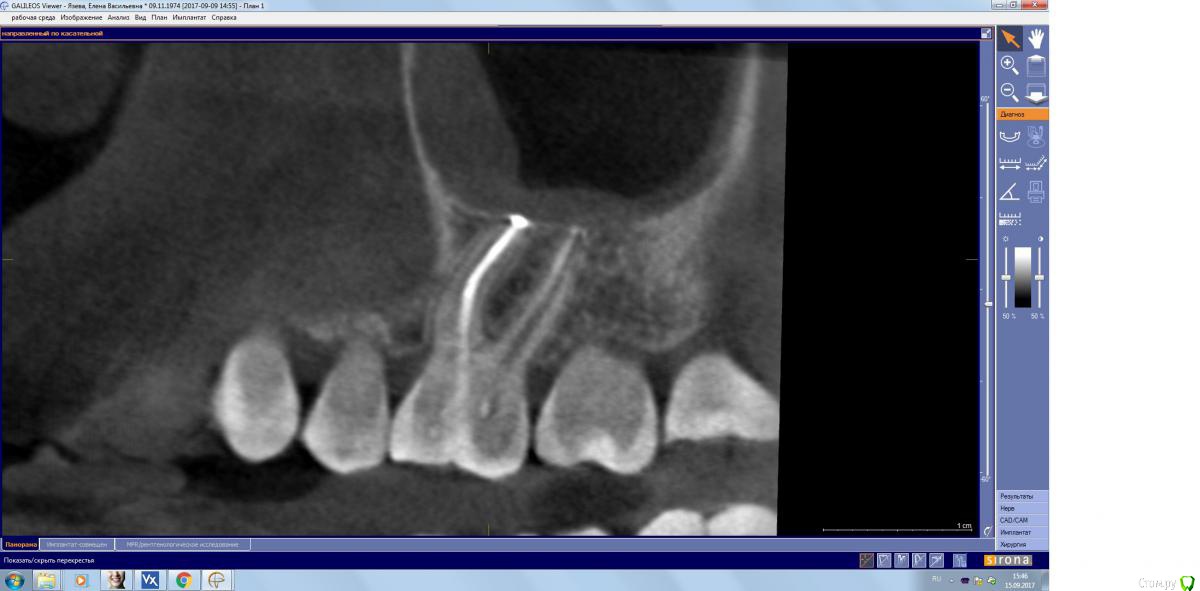

kamranchick Опубликовано 15 сентября, 2017 Поделиться Опубликовано 15 сентября, 2017 Господа, терапевт наш пролечил зуб, и болит пазуха уже месяц... сам зуб не болит, какой план действий? Ссылка на комментарий

kamranchick Опубликовано 15 сентября, 2017 Автор Поделиться Опубликовано 15 сентября, 2017 (изменено) Лор говорит хронический гайморит в стадии обострения, но провоцирует зуб, короче все как всегда... Изменено 15 сентября, 2017 пользователем kamranchick Ссылка на комментарий

kamranchick Опубликовано 15 сентября, 2017 Автор Поделиться Опубликовано 15 сентября, 2017 хотя бы узнать, это по нашей части, вернее мы виноваты или это со стороны лор что то, куда пациента определять... или опять в зуб лезть Ссылка на комментарий

parallax Опубликовано 16 сентября, 2017 Поделиться Опубликовано 16 сентября, 2017 Это пристеночно-гиперпластическая форма гайморита, застарелая хронь, которая появилась не вчера. Возможно, обострение спровоцировали паффы (куда ж без них). Я думаю, стоматологи тут не при чём. Хотя ЛОРики всегда обвиняют нас (скоро вменят убийство Кеннеди). В каналы лезть больше не надо, отправляйте в ЛОР отделение, лечение этого гайморита хирургическое. 1 Ссылка на комментарий